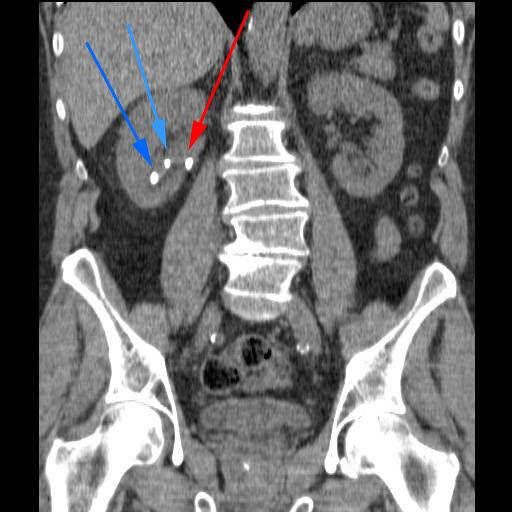

I prinsippet kan stein i alle deler av de øvre urinveier behandles. Den ideelle situasjonen er stein i nyren med samlet steinmasse mindre enn 2,5 cm i diameter, eller stein i øvre eller nedre del av urinlederen (ureter) når det ellers er normale forhold i urinveiene.

Sjokkbølger er lydbølger. Når lydbølgene treffer en nyrestein, vil energien som overføres til steinen, medføre at den knuses. Bølgene lages i en generator ("kanon") utenfor kroppen. Legen kan sikte inn slik at lydbølgene treffer nyresteinen. Som pasient ligger du på et behandlingsbord, og legen har foruten generatoren tilgang til et røntgen- eller ultralydapparat for å kunne lokalisere steinen og sikte inn mot den.